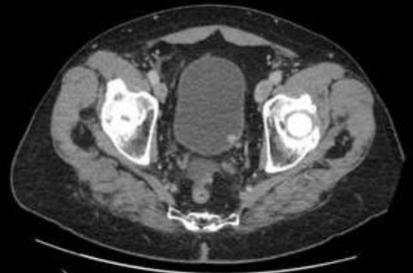

En relación con la patología que se observa en la imagen:

es correcto que:

- Su forma de debut más frecuente es un sangrado menstrual.

- La citología no es útil en el diagnóstico pero sí en el seguimiento.

- Es más frecuente en mujeres jóvenes.

- Uno de los factores de riesgo más importantes es el tabaco.

Respuesta correcta: Uno de los factores de riesgo más importantes es el tabaco.